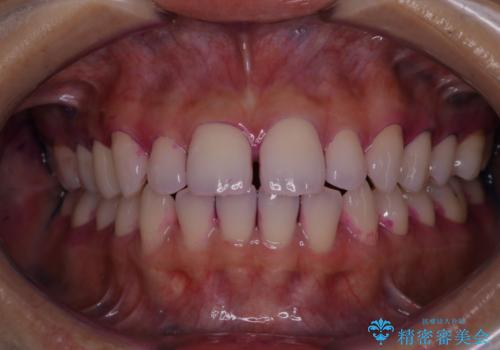

一見きれいに見える歯でも、染め出し(歯垢染色液)を使うとこのように歯と歯茎の境目や、歯と歯の間などに磨き残しがあることがわかります。歯磨きには、いつも気をつけているから磨き残しはナシと思っていても、実際完璧に磨ききることはなかなか難しいです。歯科医院にて、専門の機械で定期的なPMTCを行うことが大切です。